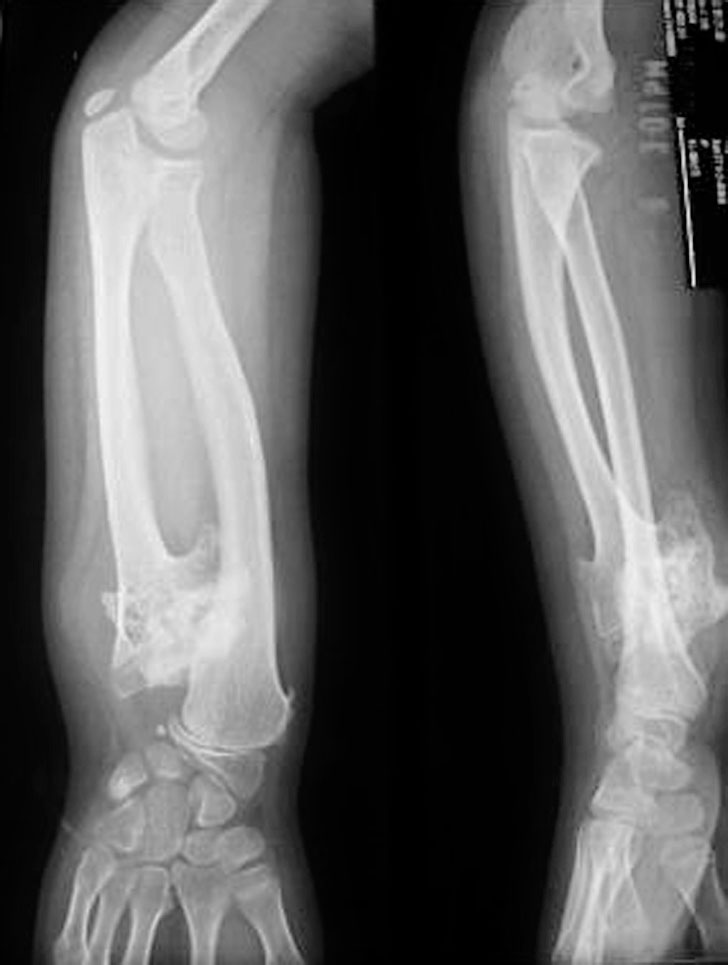

(3)桡、尺骨全长融合(图1-2-23)。

图1-2-23 右前臂桡、尺骨全长融合